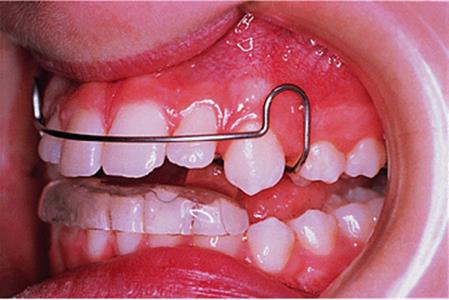

The appliance holds the mandible in a forward postured position, in this case with the incisors edge to edge (Fig. 18.1(f)). The facial musculature is thus stretched, and applies a posterior force to the upper arch and an anterior force to the lower arch. The lower incisors have acrylic capping to prevent excessive labial tilting of the lower incisors, and this also serves as a bite-plane to reduce the overbite (Chapter 10). The appliance must be worn for at least 14–16 hours each day, but once the overjet has been reduced fully the amount of daily wear can gradually be reduced to sleeping hours only. The patient should continue to wear the appliance overnight in this way as a retainer, at least until the period of rapid pubertal growth is complete. Figures 18.1(g) and 18.1(h) show the dental and facial changes which occurred during treatment.

Fig. 18.1. (a) This 12-year-old girl had a skeletal II facial pattern and average facial proportions. The lips were incompetent with the lower lip lying below the upper incisors at rest. (b), (c) She had a Class II division 1 malocclusion with an overjet of 10 mm, the overbite was increased and complete, and the molar relationship was Class II on both sides. (d), (e) The upper and lower arches were well aligned. (f) A functional appliance (an activator) was fitted. (g) The corrected occlusion with Class I incisor and molar relationships. (h) The patient's facial profile at the end of treatment.

18.5.1. The Andresen activator

There are many variations upon Andresen's original design. An Andresen activator is shown in Fig. 18.5. It is a monoblock design, that is to say it comprises upper and lower acrylic appliances fused together. The original design had a solid palate, but that shown has been made with an open palate to reduce its bulk. The lower incisors are capped to minimize the tendency for them to procline during overjet reduction, and which also serves as a bite-plane to reduce the overbite. The capping resists tipping of the teeth so that any labial movement will have to be bodily translation and is therefore minimized. The labial bow lies passively against the upper incisors, and the palatal wire is again intended to minimize palatal tilting of the upper incisors.

Fig. 18.5. Andresen activator used to treat the patient shown in Fig. 18.1.